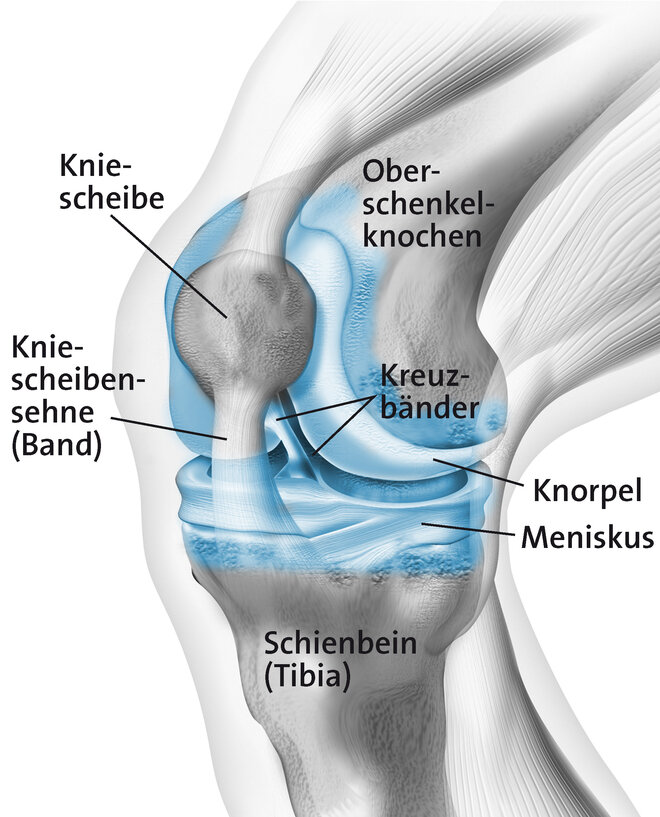

Durch Überbelastung der Kniescheibensehne (Patellarsehne) kommt es an ihrem Ursprung am Unterrand der Kniescheibe zu kleinsten Verletzungen und Auffaserungen der Sehne. In der Nähe bildet sich neues Bindegewebe, Nerven und Blutgefäße sprießen ein. Ärzte sprechen auch von degenerativen Veränderungen. Der allgemeine Fachbegriff ist Tendinopathie (= Sehnenleiden). Zu einer Überlastung der Patellarsehne kommt es vor allem durch sportliche Aktivität, insbesondere bei sogenannten Schnellkraft-Sportarten mit raschen Richtungswechseln, abruptem Abbremsen ("stop and go") und starker Belastung beim Springen und Landen wie beispielsweise Volleyball oder Handball. Daher auch der Begriff Springerknie (englisch: jumpers knee). Betroffen können ein oder beide Knie sein. Meist ist die Sehne am unteren Pol der Kniescheibe betroffen (Insertionstendinose).

Tendinopathien, also Schmerzen an den Sehnen können an verschiedenen Stellen auftreten. Beim Jumpers-Knee handelt es sich um eine Entzündung am Ansatz der Sehne (Insertionstendinose) am unteren Pol der Kniescheibe. Diese tritt vor allem beim sportlichen Erwachsenen auf. Treten die Beschwerden bereits beim Jugendlichen auf handelt es sich meist um einen Morbus Sinding-Larson-Johansen. Auch hierbei kommt es durch Überbelastung zu einer Entzündung am Ursprung der Patellarsehne, bei welcher aber ein Teil der Kniescheibe mitabsterben kann (Osteonekrose).

Hintergrundinformation - Das Kniegelenk

Das Springerknie gehört zu den orthopädischen Überlastungssyndromen. Syndrom steht für ein Krankheitsbild mit mehreren, mehr oder minder typischen Symptomen. Sowohl die Intensität als auch die Art der Belastung spielen bei dem Knieproblem eine entscheidende Rolle. So führen starke Belastungen durch zu intensives, zu häufiges oder ungewohntes Training im Sport und Bewegungsabläufe mit schnellen Richtungswechseln, Sprüngen und abruptem Abbremsen (stop and go) zu kleinsten Schädigungen und Auffaserungen der Kniescheibensehne. Mediziner sprechen hier auch von Degeneration. Zunächst findet sich eine Störung der Blutzirkulation im Gewebe, eine begleitende Entzündungsreaktion kann hinzukommen. Ungünstig sind nicht nur abrupte Zugbelastungen beim Springen, sondern auch beim Landen nach dem Sprung. Das Gleitgewebe um die Sehne herum kann ebenfalls in den Verschleißprozess eintreten. Bei anhaltenden Belastungen können die Mikro-Verletzungen auch in einen Sehnenriss münden.